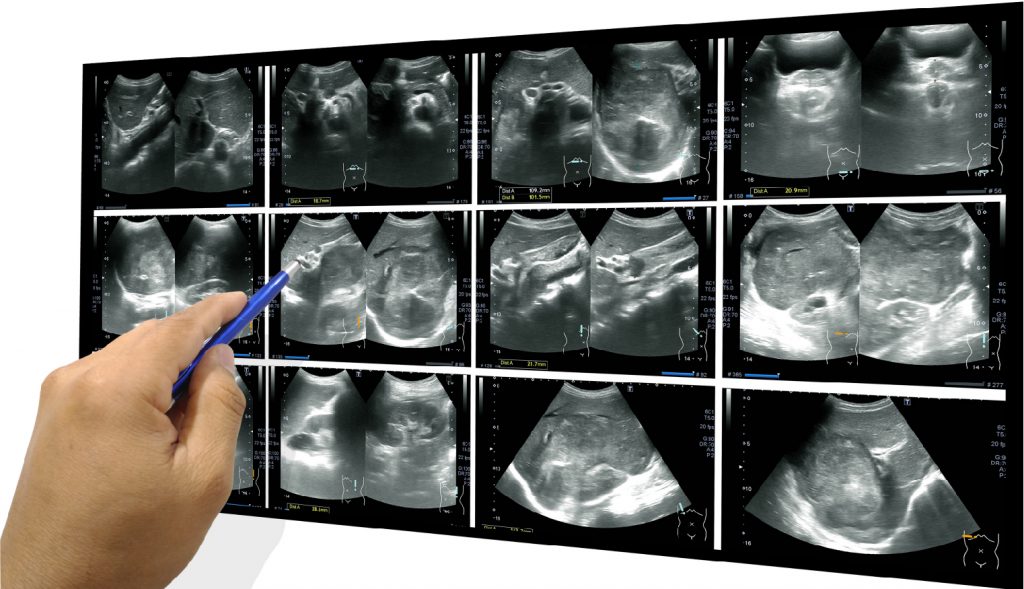

เพราะการอัลตร้าซาวด์ เป็นการตรวจวินิจฉัยโรคด้วยการใช้คลื่นเสียงกำลังสูงสะท้อนให้เกิดภาพ จึงทำให้เห็นความผิดปกติของอวัยวะต่าง ๆ ได้ชัดเจน วินิจฉัยโรคได้แม่นยำมากขึ้น และสามารถรักษาได้ตรงจุดและทันท่วงที

การอัลตร้าซาวด์แบ่งเป็น 2 ส่วน คือ

- อัลตร้าซาวด์ช่องท้องส่วนบน (Ultrasound Upper Abdomen)

- ได้แก่ ตับ ตับอ่อน ม้าม ถุงน้ำดี ท่อน้ำดี ไต ช่องท้องทั่วไป และเส้นเลือดต่าง ๆ

- สามารถตรวจหานิ่วในถุงน้ำดี นิ่วในทางเดินปัสสาวะ การตีบ-ตันของเส้นเลือดใหญ่ในช่องท้อง และไขมันพอกตับ เป็นต้น

- อัลตร้าซาวด์ช่องท้องส่วนล่าง (Ultrasound Lower Abdomen)

- ได้แก่ มดลูก รังไข่ ต่อมลูกหมาก กระเพาะปัสสาวะ ไส้ติ่ง และบริเวณช่องท้องส่วนล่างอื่น ๆ

- สามารถตรวจหาถุงน้ำรังไข่ (ซีสต์) ก้อนเนื้อในมดลูก ไส้ติ่งอักเสบ และภาวะต่อมลูกหมากโต เป็นต้น

เพื่อการตรวจวินิจฉัยได้อย่างครอบคลุมและต่อเนื่องของอวัยวะภายในช่องท้องที่เกี่ยวข้อง ควรเลือกตรวจอัลตร้าซาวด์ช่องท้องทั้งหมด (Ultrasound Whole Abdomen) ซึ่งเป็นการตรวจช่องท้องทั้ง 2 ส่วนในคราวเดียว